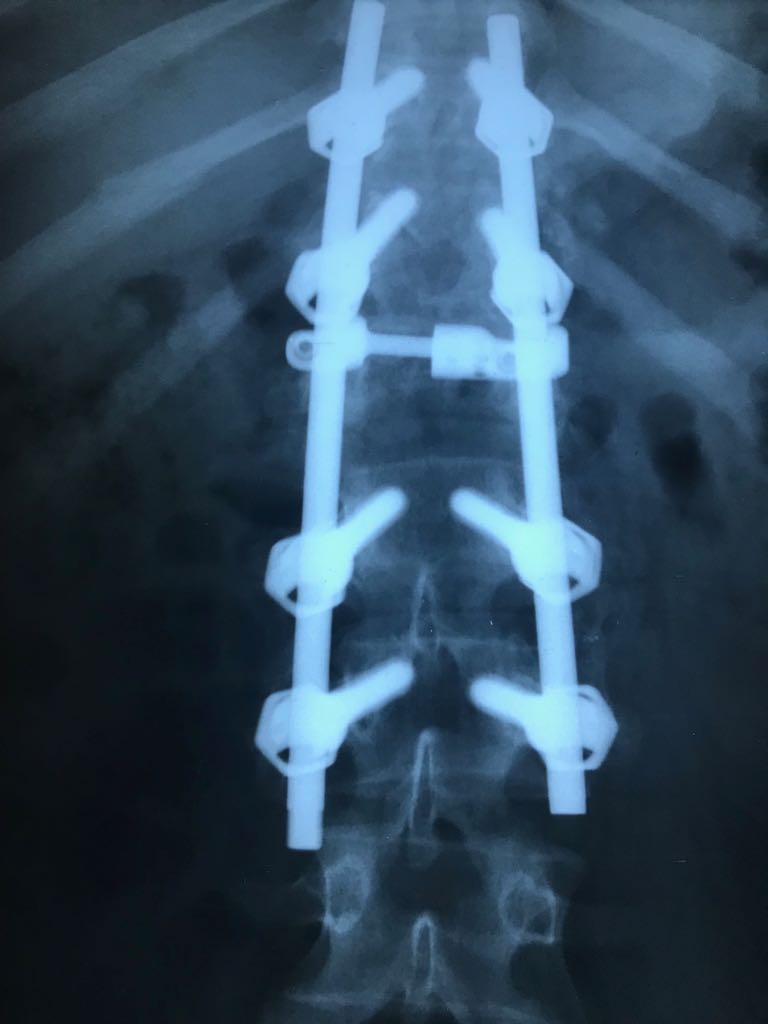

Ameliyat Sonrası